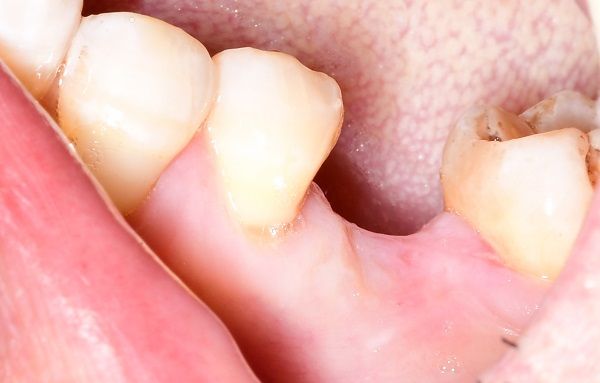

种植牙是将纯钛金属制成的人工牙根(种植体)一端通过微创外科手术植入缺牙部位的牙槽骨内,经过一段愈合期后,人工牙根和颌骨结合,再在人工牙根上镶装义齿。成功的种植牙不仅具有形态逼真、美观、舒适、咀嚼功能好、损伤邻牙等优势,还是目前理想的修复治疗方式,被誉为继乳牙、恒牙后“人类的第三副牙齿”。